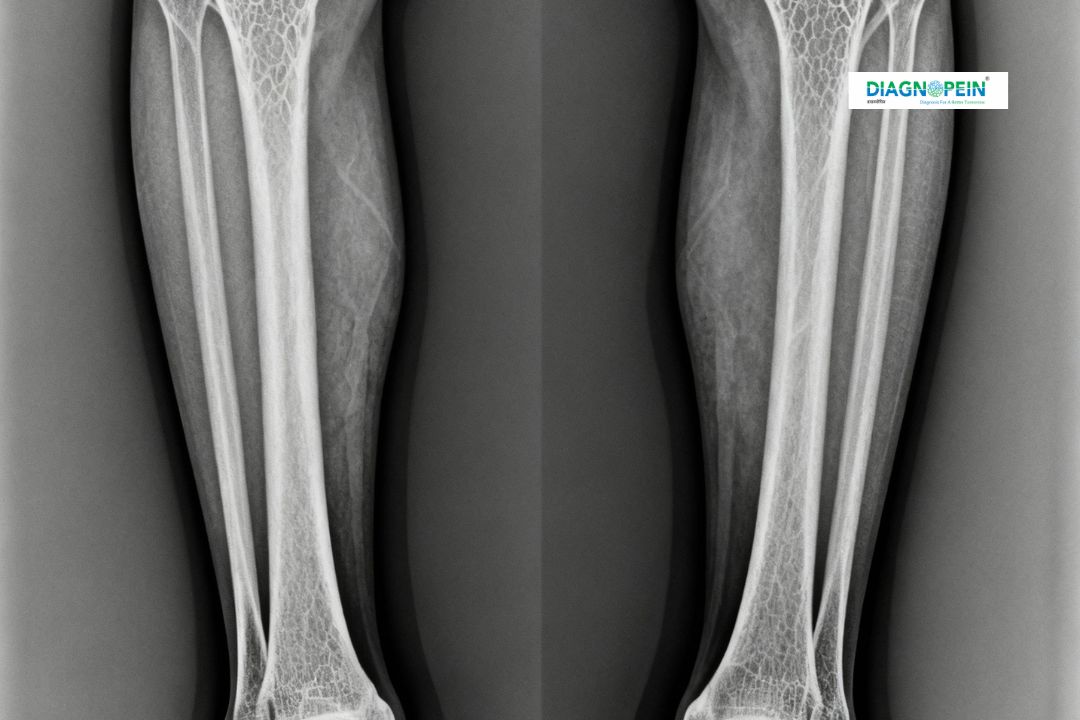

An X-Ray Both Lower Leg AP View is a diagnostic imaging test performed to visualize both lower legs together in an anteroposterior (front-to-back) view. This procedure helps assess the bones, joints, and soft tissues of the lower legs for any medical abnormalities.

This X-ray is crucial in diagnosing various bone-related problems affecting both legs. The AP (anteroposterior) view helps physicians compare both legs simultaneously, making it easier to detect irregularities, injuries, or bone alignments.

1. Detects bone fractures, cracks, or dislocations.

2. Evaluates structural deformities like bow legs or knock knees.

3. Identifies early signs of bone infections or tumors.

4. Assesses healing progress after orthopedic surgery or treatment.

5. Helps in recognizing joint space narrowing and bone density variations.

1. Bone alignment of both lower legs

2. Density and presence of fractures

3. Joint spacing and deformities

4. Presence of any foreign bodies or degenerative bone changes